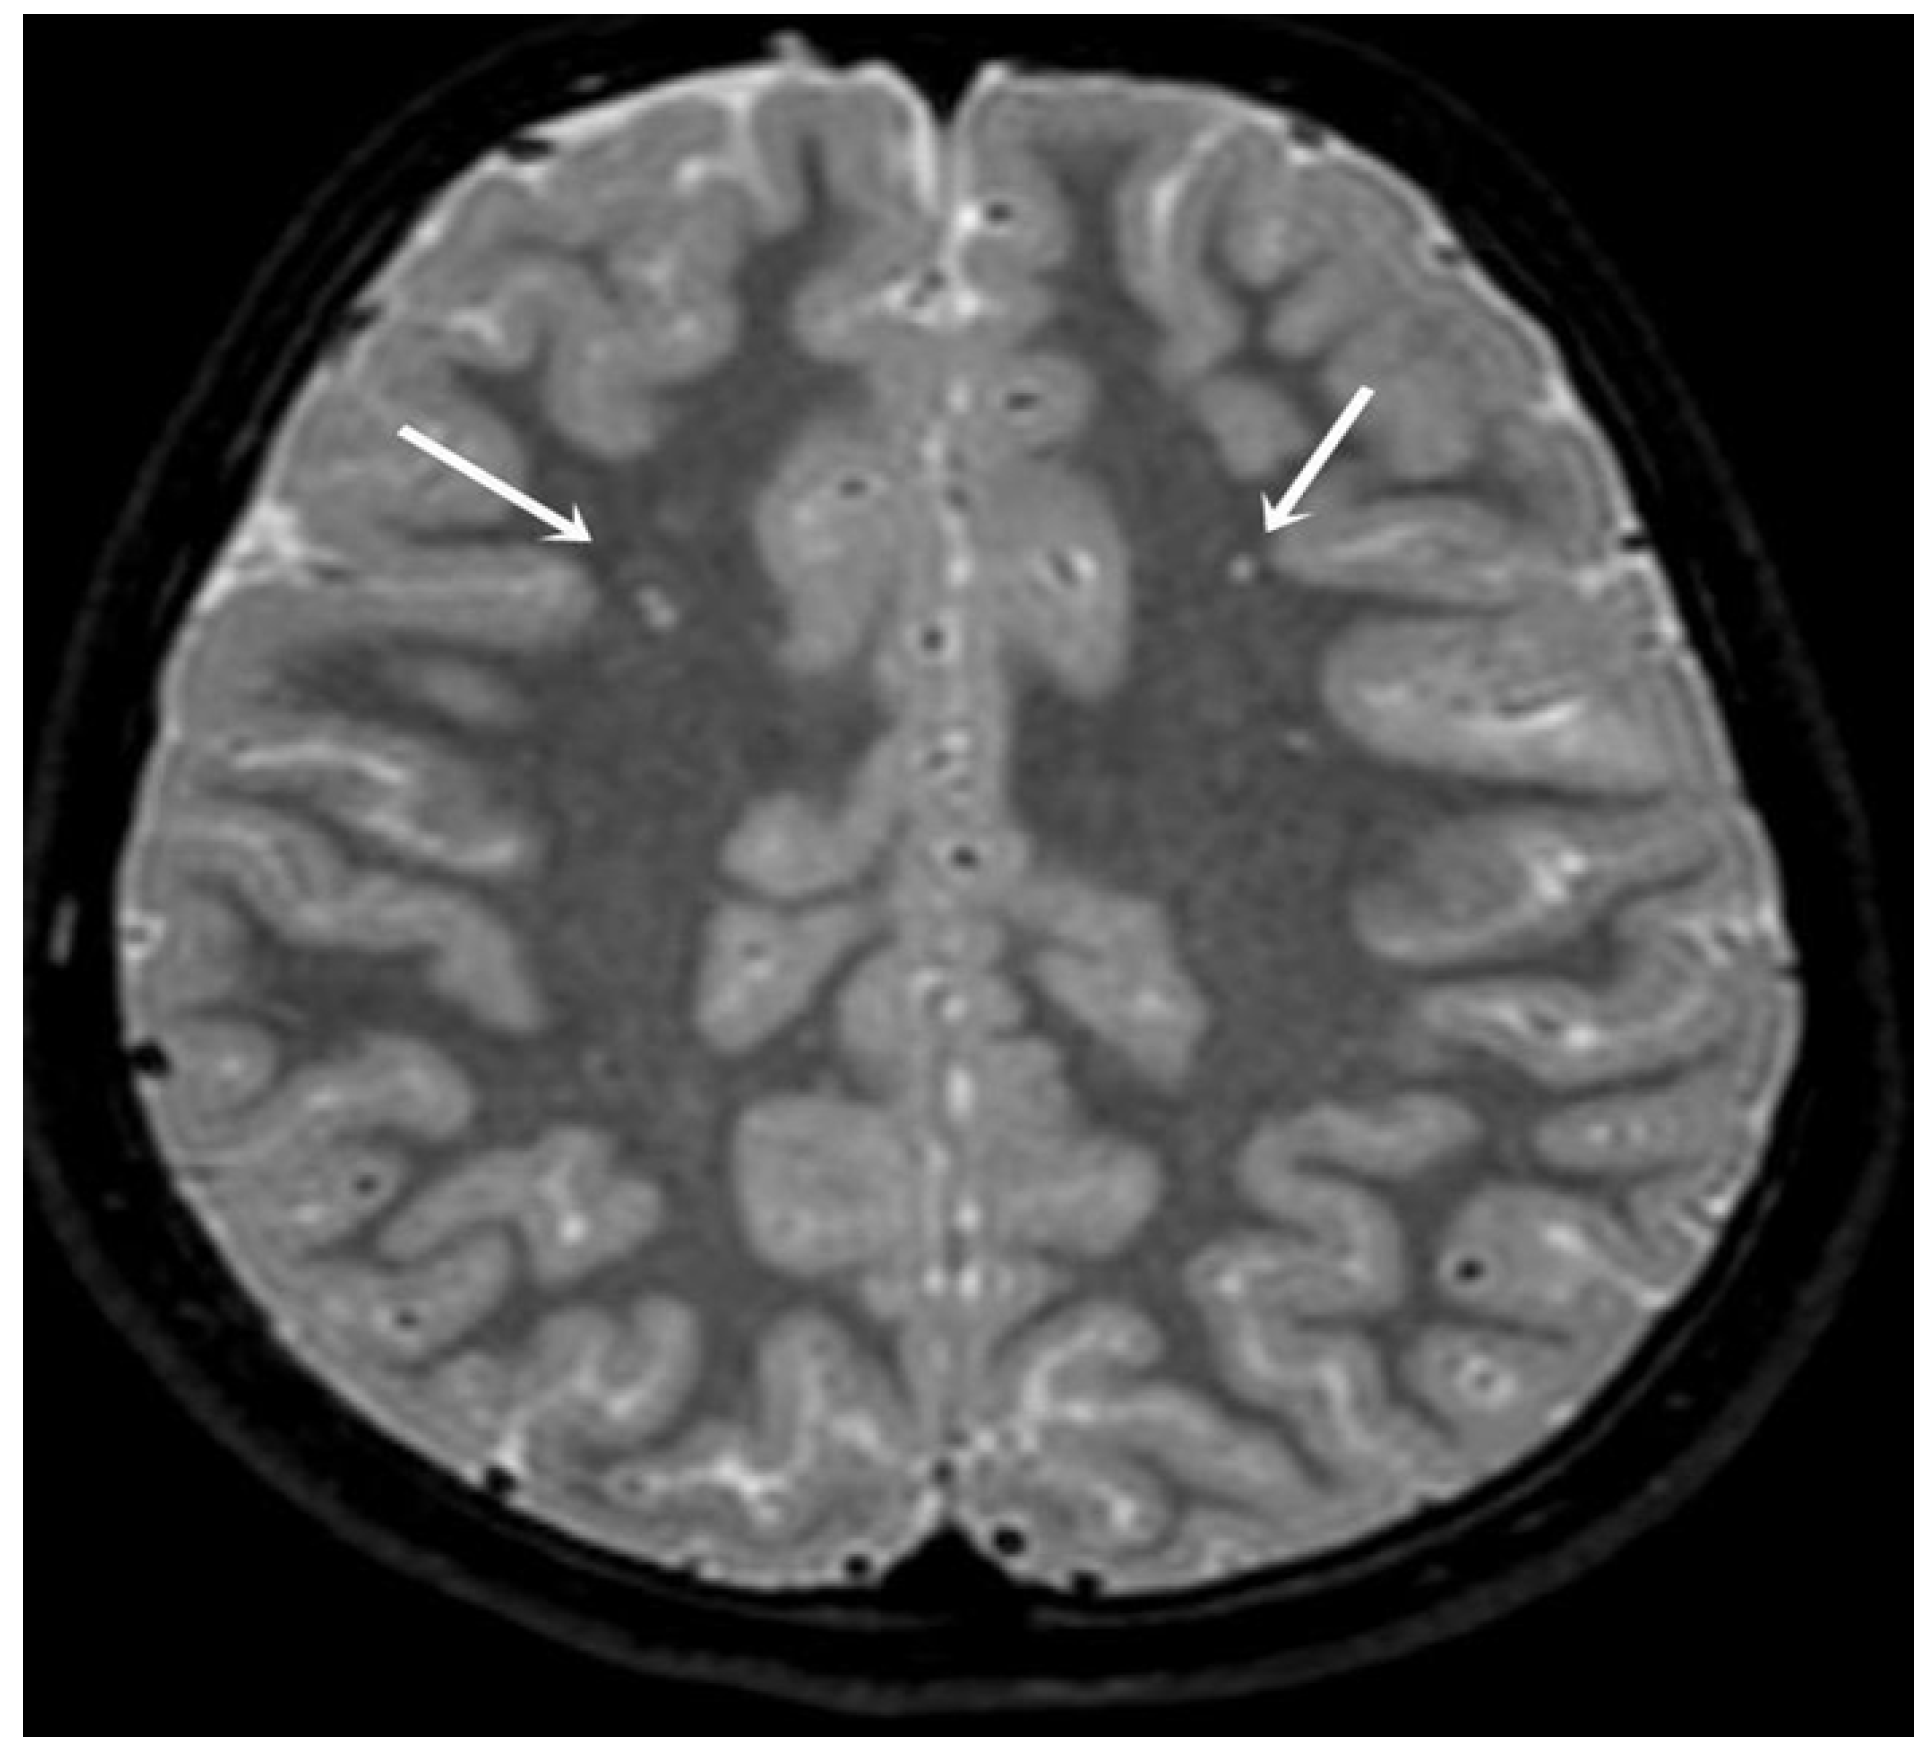

| MRI Hyperintensity n (%) | 0.016 | ||

| Yes | 8 (28.6) | 18 (60) | |

| No | 20 (71.4) | 12 (40) |

| Right frontal subcortical | 1 | 12.5 | Right frontal subcortical | 3 | 16 |

| Right frontal | 1 | 12.5 | Right frontal | 1 | 5.6 |

| Right pericallosal | 1 | 12.5 | One right, one left parietal subcortical | 1 | 5.6 |

| Left anterior frontal subcortical | 1 | 12.5 | Two left frontal subcortical | 1 | 5.6 |

| Left frontal subcortical | 1 | 12.5 | Left basal ganglia level | 1 | 5.6 |

| Left parietal subcortical | 1 | 12.5 | Left frontal subcortical | 1 | 5.6 |

| Left pericallosal | 2 | 25 | Left occipital | 1 | 5.6 |

| Left parietal | 1 | 5.6 | |||

| Left temporal | 1 | 5.6 | |||

| Four right, one left subcortical. Three of those on the right frontal, one centrum semiovale. Parietal on the left | 1 | 5.6 | |||

| Two right pericallosal | 1 | 5.6 | |||

| Two right, seven left bifrontal | 1 | 5.6 | |||

| Two left frontal subcortical | 1 | 5.6 | |||

| Two left frontal and parietal | 1 | 5.6 | |||

| Two left corpus callosum | 1 | 5.6 | |||

| Three right, five left bifrontal subcortical | 1 | 5.6 |